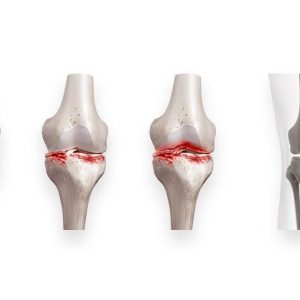

Өвдөгний үе үений үрэвсэл, мөгөөрсөний гэмтэл, чагтан холбоосын урагдал, мөгөөрсний зөөлрөл, доод мөчдийн бэхэлгээ

Зөөлөн мөгөөрсөн дээр хуралдаж үенд үүрэвсэл үүсгэн хаван,өвдөлт, үеэр хөндүүрлэж өвдөх шинж тэмдэг голдуу настай хүмүүст хамт илэрч, үенд үүссэн шарх ба халдвараар илэрдэг.